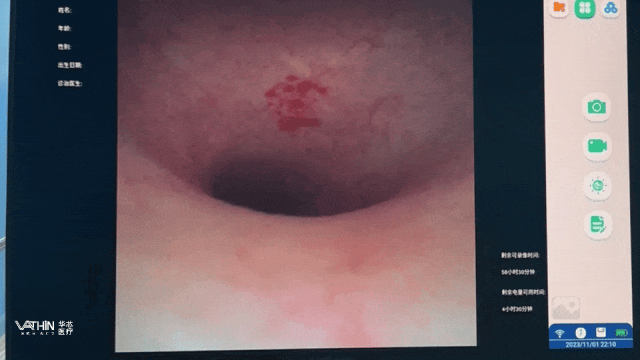

其中,华芯医疗无疑是该赛道值得关注的明星企业。以泌尿系结石诊疗为例,凭借超1200项的技术创新与研发专利,该公司能够为碎石诊疗提供更全面的一站式解决方案。其推出的华芯一次性软镜平台,实现6.3Fr/7.5Fr/8.4Fr多规格赋能,重新定义软镜碎石新时代。

从产品优势角度出发,以“一次性电子输尿管肾镜导管-6.3Fr”为例,基于约2.1mm的超细镜体,能够轻松通过狭窄输尿管,进而显著降低输尿管黏膜损伤风险。此外,通过搭配9fr的导引鞘,以降低镜体摆动导致的鞘管移位风险,稳定灌注流量(≥40ml/min),维持清晰术野。

在当下的医疗生态中,器械的临床价值与手术者的体验感高度挂钩。“一次性电子输尿管肾镜导管-6.3Fr”兼容主流微器械,支持碎石/取石/活检操作,能有效减少器械更换次数,避免因器械卡顿导致的手术时间延长。同时,大角度双向主动弯曲(上≥285°, 下≥285°),方便探查困难肾盏,为诊疗效率和准确深度赋能。